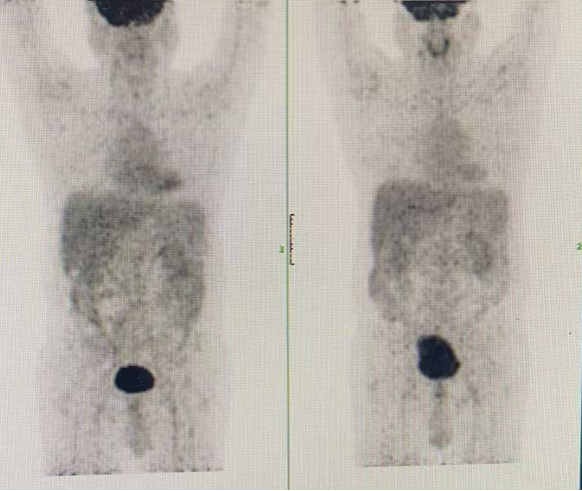

• 2025-08-02至2025-10-09,行4个周期莫妥珠单抗+泽布替尼治疗。患者在C1D15第一次输注60mg莫妥珠单抗后出现发热,体温38.6℃,周沙主治医师评估出现CRS反应1级,经对症治疗后缓解。2025-11-01查PET-CT示Deauville评分1分,疗效评估达CMR。骨髓细胞学及FISH均转阴,MRD阴性。脾脏回缩,血常规示HGB 142g/L,PLT 53×109/L,ALC 1.29×109/L;血生化示LDH 257 U/L。

2025-11-01 PET-CT